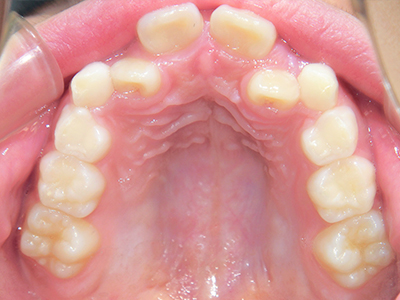

歯並びの相談に来られるお子様は、口呼吸をしているケースが多く、これが歯並びに大きな影響を与えています。

↓ - 上あごが狭くなる

↓ - さまざまな不正咬合が生じる

ないき歯科クリニックでは、上あごの成長不足を補い、鼻呼吸を獲得しつつ歯列を整え、将来のお口をより健康な状態にすることをゴールに定める矯正治療をおこなっています。